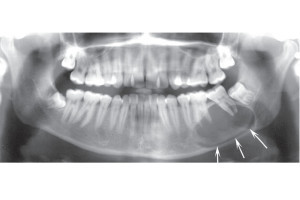

Радиационно-индуцированный некроз или остеорадионекроз характеризуется наличием обнаженной кости после проведения лучевой терапии. Открытая кость может полностью секвестрировать, что часто приводит к обнажению большего количества кости. Хотя кость, расположенная в любом месте челюсти, восприимчива к излучению, задняя часть нижней челюсти поражается чаще, чем другие области, потому что она часто находится в поле излучения, особенно когда в лечение включены лимфатические узлы. Может возникать интенсивная боль при периодическом отеке и дренировании вне полости рта. Однако многие пациенты не чувствуют боли при обнажении костей. Утрата нормальной структуры может нарушить целостность кости, а в некоторых случаях кость может сломаться.